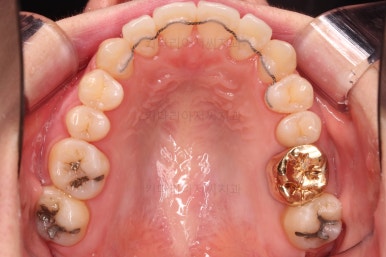

초진 시, 입안의 모습입니다.

좌측 송곳니가 덧니처럼 튀어나가 있고, 송곳니 옆의 작은 억므니가 안으로 쏙 들어가서 덧니 느낌이 더 강조되어 보이네요.

위아래 앞니가 긴밀하게 겹침이 없는 약간의 개방교합(오픈바이트, Openbite) 경향이 보입니다.

이번에 선택하신 장치는 자가결찰 세라믹 중에 엠파워 클리어라는 장치인데요.

흔히들 아시는 클리피씨도 같은 분류의 장치입니다.

철사가 들어가니 삐뚤한 치열이 더 강조되어 보이네요.